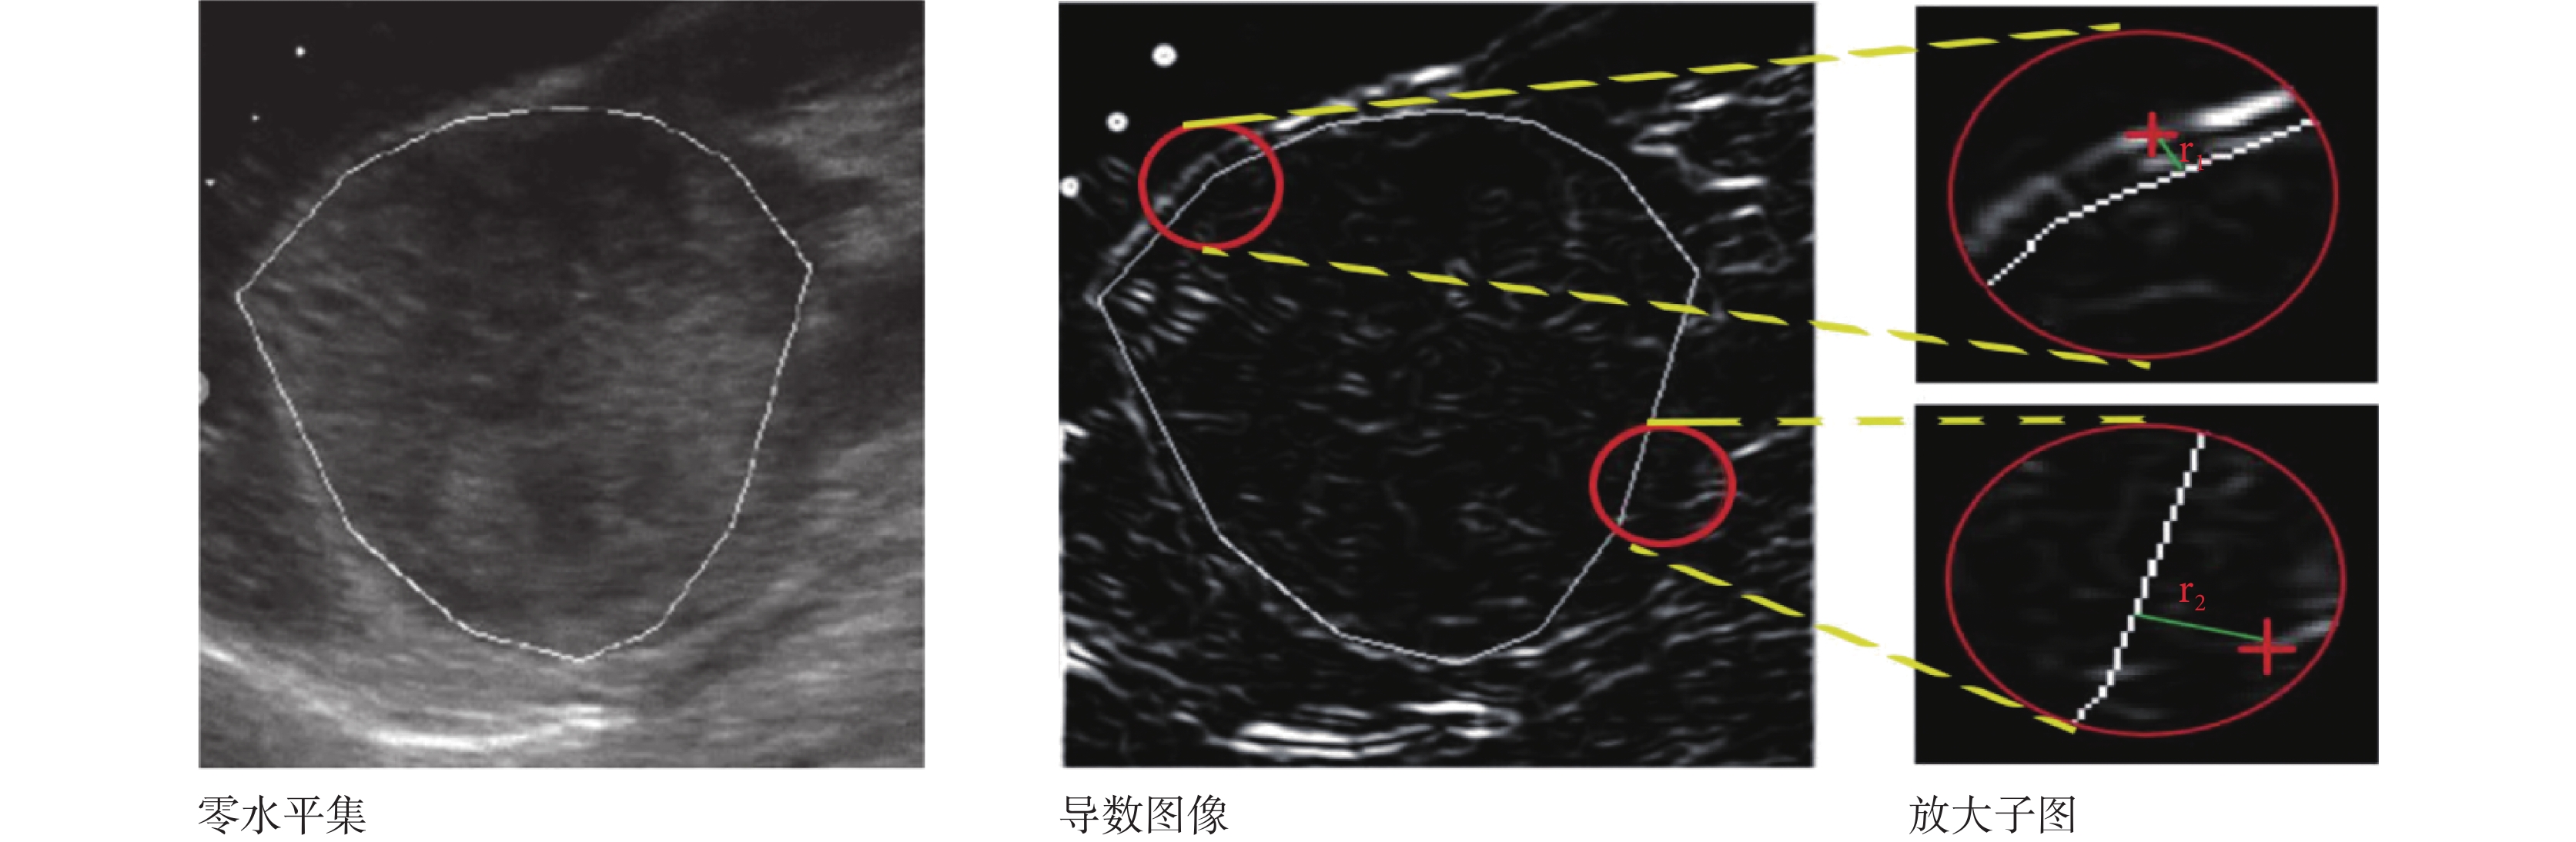

由于超聲圖像對比度低且斑點噪聲大,在同一個區域內很難找到真實的邊界梯度最大值點,故采用質心理論。如圖 4 所示原理,本文在導數圖像零水平集等間隔取圓心,以 r = 0.1?K 為半徑采樣,其中 K 為 ROI 長和寬中最小值。首先計算每個采樣子圖質心如式(16)所示;然后求得質心到最近零水平集的最短距離的平均值,即該子圖的卷積半徑;最后計算分區內所有采樣子圖卷積半徑平均值,即該分區的卷積半徑 convr(i),如式(17)所示。

如圖 7 所示,本文將 ROI 求導后得到導數圖像。紅十字即為該采樣子圖質心,計算質心到零水平集(白線)的最短距離,即該采樣子圖的卷積半徑,如放大子圖中 r1、r2;再將分區子圖卷積半徑求平均值,即該分區的卷積半徑 convr(i)。當邊界非常模糊時,若無法獲得質心位置,將所有其他區域卷積半徑的平均值賦予這個區域。1~8 分區的 convr(i)取值分別為 4.21、7.23、6.19、13.90、21.34、9.45、10.43、3.82。